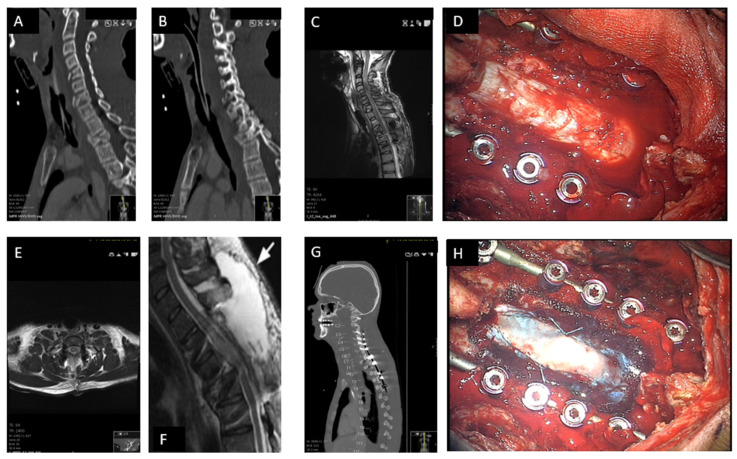

Abstract Image